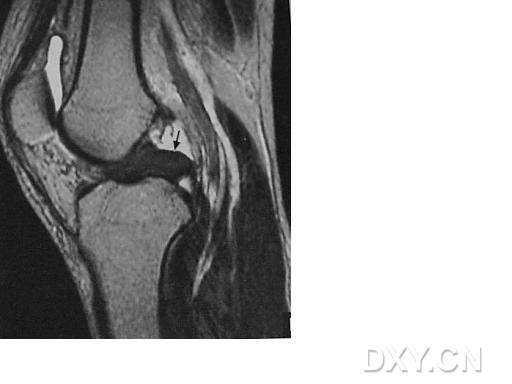

| III级 内侧半月板后角内见线形高信号达到半月板的关节面下缘